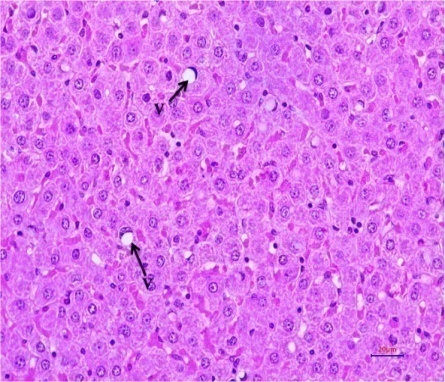

Fig. 12: Histopathological examination of experimental rat liver after 21 d treatment (HandE, 400 X magnifications). Liver section of (I) Normal control, (II)Diabetic control,(III)EOAM (EOFAE 250+AMLEAE250 mg/kg bw),(IV) EOAM (EOFAE 500+AMLEAE 250 mg/kg bw, Combination of (V)EOAM (EOFAE 500+AMLEAE250+Glib 5 mg/kg bw),(VI)EOAM (EOFAE 500+AMLEAE 250+Glib 5 mg/kg bw),(VII)Glibenclamide5 mg/kg bw.[Hepatocyte (HC), Normal Portal Triad (P), Hepatocellular Vacuolation (V), Portal Triad (P) and Hepatocyte (H)]

Histopathological studies

Histopathological examination of the experimental rat liver after 21 d treatment indicates that the liver section of normal control rats (NC) did not revealed any lesion of pathological significance as shown in fig. 12 (I). Liver section of diabetic control rat showed multifocal moderate hepatocellular vacuolation (microvesicular) as shown in fig. 12 (II). Liver section of diabetes-induced rats treated with low dose and high dose did not revealed any lesion of pathological significance as shown in fig. 12 (III) and (IV). Combination of low dose and high dose with glibenclamide also did not revealed any lesion of pathological significance as shown in fig. 12 (V) and (VI). Standard drug did not revealed any lesion of pathological significance as shown in fig. 12 (VII). Histopathology of the liver of STZ induced diabetic animals showed that there were hepatic changes, mild portal inflammation and hepatocellular vacuolation. After treatment of the animals by EOAM and glibenclamide, there was normal histology and reduced severity of the histopathological changes caused by STZ. The present study shows that the EOAM treated group III have significant antioxidant and antidiabetic activity as compare to diabetic control STZ induced animals. Equiproportion combination of both extracts shows significantly decreased in oxidative stress as evidenced by improved activities of antioxidant enzymes like superoxide dismutase, reduced glutathione. From the histological studies the liver section of group V and VI may have some interactions and liver section of diabetes-induced rats groups III, IV treated with EOAM and VII treated with well known sulfonylurea drugs like glibenclamide did not revealed any lesion of pathological significance, where the group III shows good significant effect (p<0.001) as compare to STZ-induced diabetic rats.